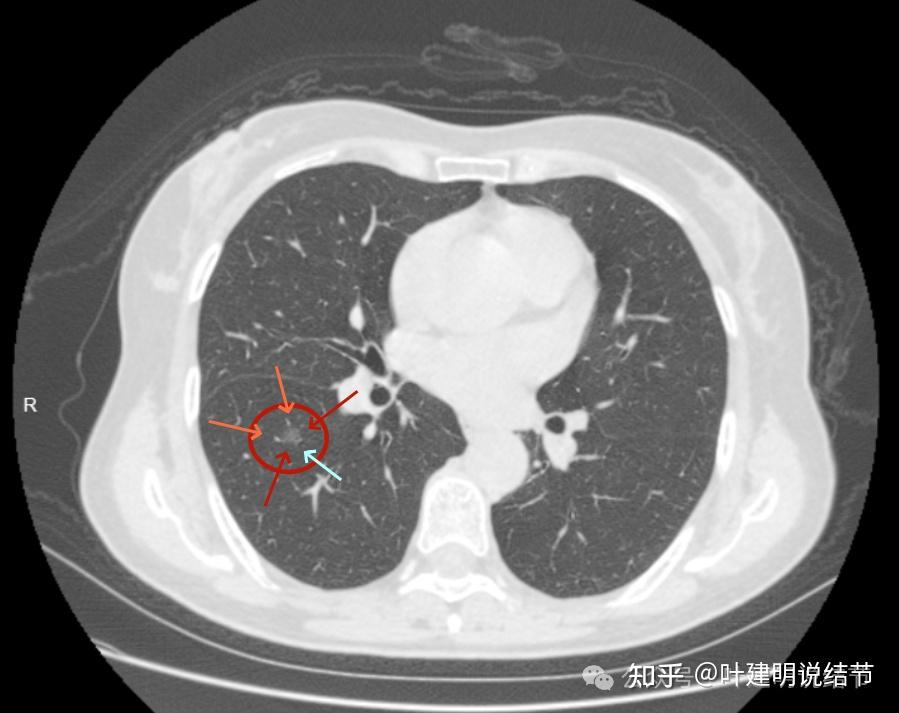

mds患者发热,ct见右肺下叶类圆形软组织影,考虑何因